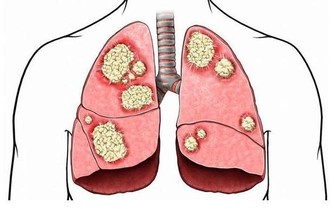

心腦血管疾病患者適合每天一杯硒谷黑苦蕎茶,主要沿用《千金要方》中的組方,具體配方適當加減。硒谷黑苦蕎茶富含黃酮類物質能抑制甘油三酯和膽固醇升高和肝臟脂質過氧化,從而降血脂;富含硒元素,硒依靠其強大的抗氧化功能,可調節體內膽固醇及甘油三酯,降低血液黏度,清除體內的有害自由基,防止人體血管老化,預防中風,預防心血管病的發生。